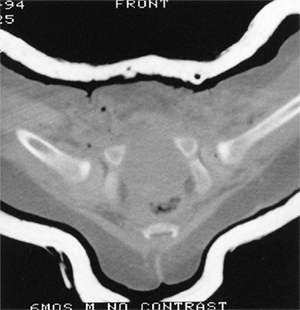

Figure 24.24

Anteroposterior radiographs made after closed reduction of developmental dislocation of the hip that had been performed when the patient was 2 years and 4 months of age. A: Thirty-nine months after reduction, when the patient was 5 years and 7 months of age, the accessory centers of ossification are visible in the acetabular cartilage. B: Fifteen years after reduction, when the patient was 17 years of age, the Shenton line is intact and there is mild, acetabular dysplasia. C: Forty-two years after reduction, when the patient was 44 years of age, degenerative changes are present. D: Fifty-one years after reduction, when the patient was 53 years of age, the hip is subluxed and shows severe degenerative changes (Iowa Hip Rating, 48 of 100 points). The patient subsequently underwent total hip replacement. (From Malvitz TA, Weinstein SL. Closed reduction for congenital dysplasia of the hip: functional and radiographic results after an average of thirty years. J Bone Joint Surg Am 1994;76:1777.) |